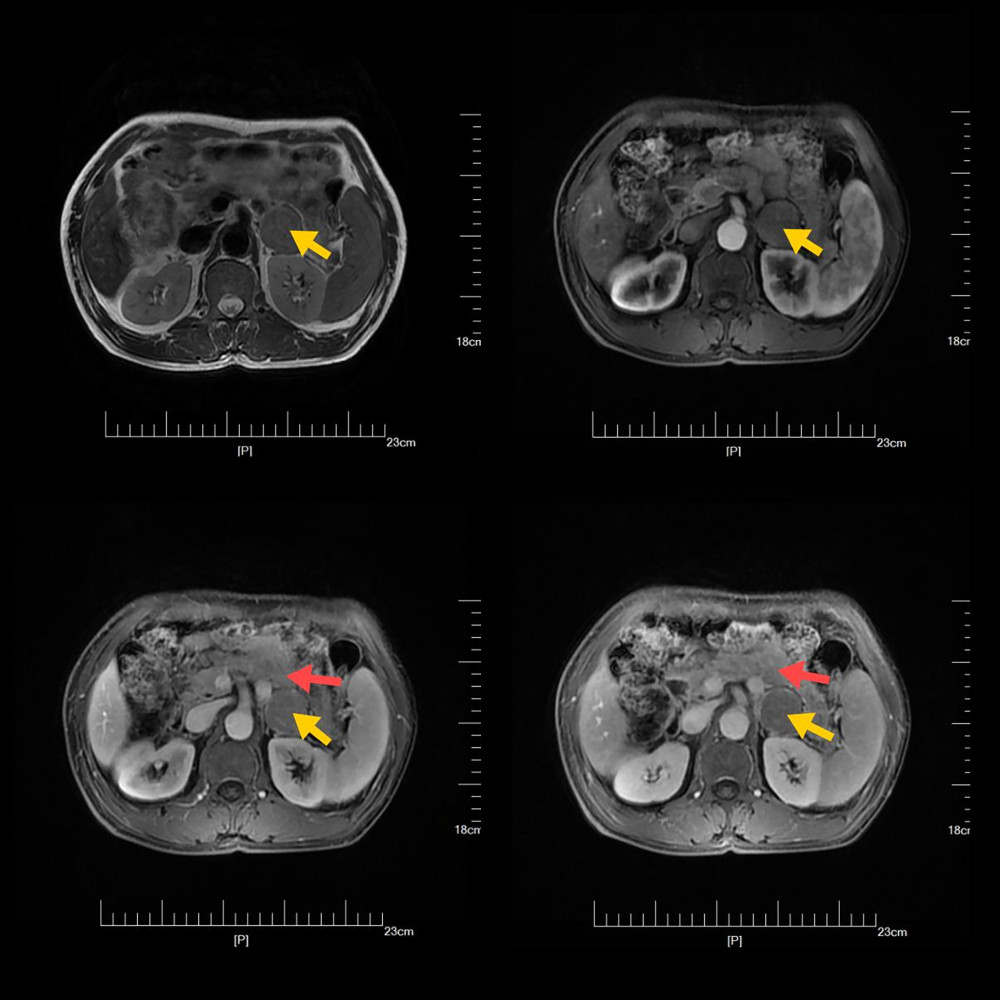

Abdominal CT (Figure 1) revealed a well-defined, 3-cm mass between the lower margin of the pancreas and the left lateral ramus of the adrenal gland; the right adrenal gland was normal. Although the radiology report did not document Hounsfield unit values, enhancement patterns and location suggested an adrenal-origin lesion. MRI (Figure 2) further characterized this as a solid-cystic mass in the same region, consistent with an ectopic adrenocortical adenoma.

Figure 1. Contrast-enhanced computed tomography axial image demonstrating a 3-cm hyper-enhancing ectopic adrenal lesion (arrow) situated between the pancreatic tail and left adrenal remnant.  Figure 2. Magnetic resonance imaging T2-weighted coronal image showing a hyperintense mass (arrow) located between the lower margin of the pancreas and the lateral branch of the left adrenal gland.

Figure 2. Magnetic resonance imaging T2-weighted coronal image showing a hyperintense mass (arrow) located between the lower margin of the pancreas and the lateral branch of the left adrenal gland.  Figure 3. Histopathological features of adrenal cortical adenoma with focal medullary hyperplasia. (A–F) Hematoxylin and eosin staining of adrenal tumor tissue sections demonstrates a clear zonal distinction between oncocytic and lipid-rich clear cells. (A, C, E) Low (100×), intermediate (200×), and high magnification (400×) views showing oncocytic cells with eosinophilic, granular cytoplasm, and sparse lipid droplets (black arrows). These cells are arranged in solid nests and trabeculae. (B, D, F) Corresponding magnifications highlighting lipid-rich clear cells (black arrows), characterized by vacuolated, optically clear cytoplasm and peripherally displaced nuclei. Notably, focal adrenal medullary hyperplasia is observed interspersed among cortical elements, indicating mixed histological features.